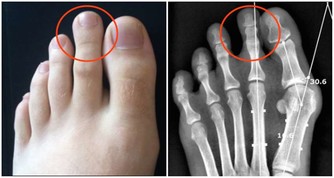

5關節痛

每天早上起床後吃幾片生薑或者煮姜棗水喝,一日3次堅持吃能明顯緩解關節的疼痛。